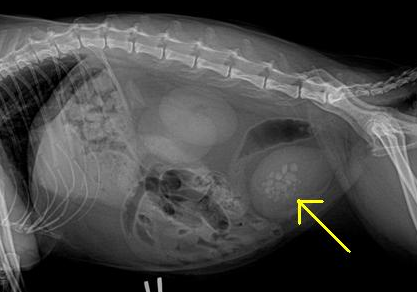

X光明顯看到膀胱當中有結石(取自http://exclusivelycats.blogspot.tw/)